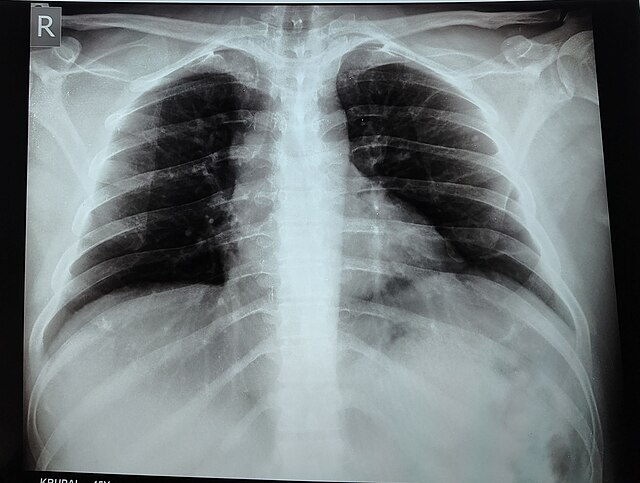

जौनपुरवासियों, जब भी हमारे शहर में किसी को अचानक चोट लगती है या हड्डी के दर्द की चिंता होती है, तो डॉक्टर अक्सर सबसे पहले एक्स-रे (X-Ray) कराने की सलाह देते हैं। यह सरल-सी सलाह हमें याद कराती है कि सौ से अधिक वर्षों पुरानी यह तकनीक आज भी हमारे जीवन का एक महत्वपूर्ण हिस्सा है। तो आइए आज जौनपुर की धरती से ही इस पूरी वैज्ञानिक यात्रा को समझने की कोशिश करते हैं, जिसमें हम एक्स-रे की शुरुआत, उसके विकास और आज एआई (A.I.) की मदद से उसके आधुनिक रूप को जानेंगे। इसके साथ ही, हम यह भी महसूस करेंगे कि इन बदलावों ने हमारे शहर में इलाज को कितना तेज़, भरोसेमंद और सुरक्षित बनाया है।

आज के इस लेख में हम चार बातों को क्रम से समझेंगे। सबसे पहले, हम जानेंगे कि एक्स-रे की खोज कैसे हुई और वैज्ञानिकों ने इस रहस्यमयी किरण को कैसे पहचाना। इसके बाद, हम एक्स-रे इमेजिंग के इतिहास में हुए प्रमुख विकासों की यात्रा पर चलेंगे। फिर हम यह समझेंगे कि एआई एक्स-रे छवियों के पैटर्न को कैसे पहचानता है और किस तरह यह डॉक्टरों की सहायता में एक महत्वपूर्ण भूमिका निभा रहा है। अंत में, हम देखेंगे कि आज रेडियोलॉजी (Radiology) में एआई का सहयोग हमारे जैसे शहरों में इलाज को कैसे बेहतर बना रहा है।

एक्स-रे का आविष्कार कैसे हुआ

एक्स-रे तरंगें हमेशा से अस्तित्व में थीं, लेकिन 19वीं सदी के अंत तक वैज्ञानिकों ने इन अदृश्य तरंगों के महत्व को नहीं पहचाना था। इस खोज की नींव बहुत पहले 1785 में पड़ी, जब विलियम मॉर्गन (William Morgan) ने अपने प्रयोग के दौरान एक चमकीली हरी रोशनी देखी। उन्होंने इस अवलोकन को रॉयल सोसाइटी (Royal Society) के सामने रखा, लेकिन इसकी वास्तविक प्रकृति लंबे समय तक रहस्य बनी रही।इसके बाद 1800 के दशक के उत्तरार्ध में वैज्ञानिकों ने कैथोड किरणों और निर्वात नलियों पर काम करना शुरू किया। क्रुक्स नली (Crooks Hose) ने इलेक्ट्रॉनों (electrons) की गति और व्यवहार को समझने का रास्ता खोला। 1888 में फिलिप लेनार्ड (Philip Lennard) ने पाया कि कैथोड किरणें एल्यूमीनियम फॉइल (aluminum foil) पार कर सकती हैं और अंधेरे कमरे में रखी स्क्रीन को चमका सकती हैं। यह अवलोकन एक्स-रे की समझ की दिशा में एक बड़ा कदम था।कुछ वर्षों बाद 1895 में जर्मन वैज्ञानिक विल्हेम कॉनराड रॉन्टगन (Wilhelm Conrad Rontgen) ने यह समझने के लिए प्रयोग किया कि क्या कैथोड किरणें कांच से गुजर सकती हैं। उन्होंने देखा कि एक ढकी हुई नली के पास रखी स्क्रीन चमक रही है, जबकि वहाँ कोई सामान्य प्रकाश नहीं था। उन्होंने परिकल्पना की कि कोई नई किरण पैदा हो रही है, जो न सिर्फ़ कांच से बल्कि कागज़, लकड़ी और एल्यूमीनियम फॉइल से भी गुजर सकती है। रॉन्टगन ने अपनी पत्नी के हाथ का पहला एक्स-रे चित्र लिया, जिसमें उसकी हड्डियाँ और धातु की अंगूठी साफ़ दिखाई दे रही थी। इसी अद्भुत खोज के कारण उन्हें 1901 में भौतिकी का पहला नोबेल पुरस्कार मिला, जिसे उन्होंने अपने विश्वविद्यालय को दान कर दिया। यही वह क्षण था जिसने चिकित्सा की दुनिया को हमेशा के लिए बदल दिया।

इतिहास में एक्स-रे इमेजिंग का विकास

रॉन्टगन की खोज के बाद एक्स-रे इमेजिंग लगातार विकसित होती रही। वर्ष 1875 में क्रुक्स कैथोड रे (Crookes Cathode Ray) नली का आविष्कार हुआ, जिसने आगे के प्रयोगों को आधार दिया। 1895 में रॉन्टगन द्वारा एक्स-रे की खोज के बाद 1900 में थॉमस एडिसन (Thomas Edison) ने फ्लोरोस्कोपी (Fluoroscopy) विकसित की, जो वास्तविक समय में चिकित्सा प्रक्रियाओं को देखने में सहायक थी। 1913 में आधुनिक एक्स-रे नली का निर्माण हुआ और इसी वर्ष स्तन ऊतक का पहला समर्पित रेडियोग्राफ तैयार किया गया।1918 में एक्स-रे फिल्में आईं, जिससे जांच और स्पष्ट और आसान हो गई। 1930 के दशक में नैदानिक मैमोग्राफी और 1932 में पहली एक्स-रे टोमोग्राफी (Tomography) सामने आई। इसके बाद 1953 में सब्ट्रैक्शन इमेजिंग और 1980 में डिजिटल सब्ट्रैक्शन एंजियोग्राफी (Subtraction Angiography) ने रेडियोलॉजी को और आधुनिक बनाया। 1983 में कंप्यूटेड रेडियोग्राफी (computed radiography) और 2000 के दशक में डिजिटल डिटेक्टरों (digital detectors) ने जांच की गति और सटीकता को और बढ़ा दिया। यह संपूर्ण विकास आज जौनपुर में मिलने वाले तेज़ और भरोसेमंद एक्स-रे परीक्षणों की नींव है, जिससे डॉक्टर बहुत कम समय में स्पष्ट निर्णय ले पाते हैं।

एआई के माध्यम से एक्स-रे पैटर्न की पहचान

आज एक्स-रे के आधुनिक स्वरूप में एआई यानी कृत्रिम बुद्धिमत्ता का योगदान बहुत महत्वपूर्ण है। एआई मॉडल, विशेष रूप से कॉन्वोल्यूशनल न्यूरल नेटवर्क, बड़ी संख्या में एक्स-रे छवियों पर प्रशिक्षित किए जाते हैं। इससे वे छवि में मौजूद पैटर्न को पहचानना सीखते हैं, जैसे कि फॉल्ट लाइन्स (fault lines), असामान्य आकृतियाँ या संभावित फ्रैक्चर। एआई छवि में उन क्षेत्रों को पहचान लेता है जहाँ समस्या होने की संभावना होती है। कई मॉडलों को मिलाकर तैयार किए गए एन्सेम्बल सिस्टम (Ensemble System) निर्णय की सटीकता को और बढ़ाते हैं। ध्यान तंत्र एआई को छवि के उचित हिस्सों पर केंद्रित रहने में मदद करता है, ताकि सूक्ष्म से सूक्ष्म फ्रैक्चर भी न छूटे। कई अध्ययनों में यह साबित हुआ है कि एआई कभी-कभी विशेषज्ञ रेडियोलॉजिस्ट जितनी सटीकता प्राप्त कर सकता है। हालांकि यह पूरी तरह डॉक्टर का विकल्प नहीं है, बल्कि एक ऐसा सहयोगी है जो डॉक्टर के काम को आसान और तेज़ बनाता है। जौनपुर जैसे शहरों में, जहाँ तेज़ और सटीक जांच की आवश्यकता होती है, एआई एक महत्वपूर्ण भूमिका निभा रहा है।

रेडियोलॉजी में एआई कैसे सहयोग कर रहा है

रेडियोलॉजी में एआई का उपयोग डॉक्टरों के लिए समय और सटीकता दोनों में मददगार साबित हुआ है। एआई मरीजों की स्थिति के आधार पर स्कैन की प्राथमिकता तय कर देता है, जिससे गंभीर मामलों का निदान पहले होता है। कई बार एआई मानव आंखों से भी अधिक सटीकता से असामान्यताओं को पहचान लेता है। एआई द्वारा अनुकूलित रेडियोलॉजी प्रक्रिया मरीजों और रेडियोग्राफरों को कम विकिरण के संपर्क में लाती है। रिपोर्ट निर्माण भी अब तेज़ और मानकीकृत हो चुका है, जिससे उपचार जल्द शुरू हो पाता है। इसके अलावा, छवि की गुणवत्ता में सुधार के कारण छोटे से छोटे बदलाव भी सामने आ जाते हैं, जिससे बीमारी को जल्दी पकड़कर इलाज समय पर किया जा सकता है।